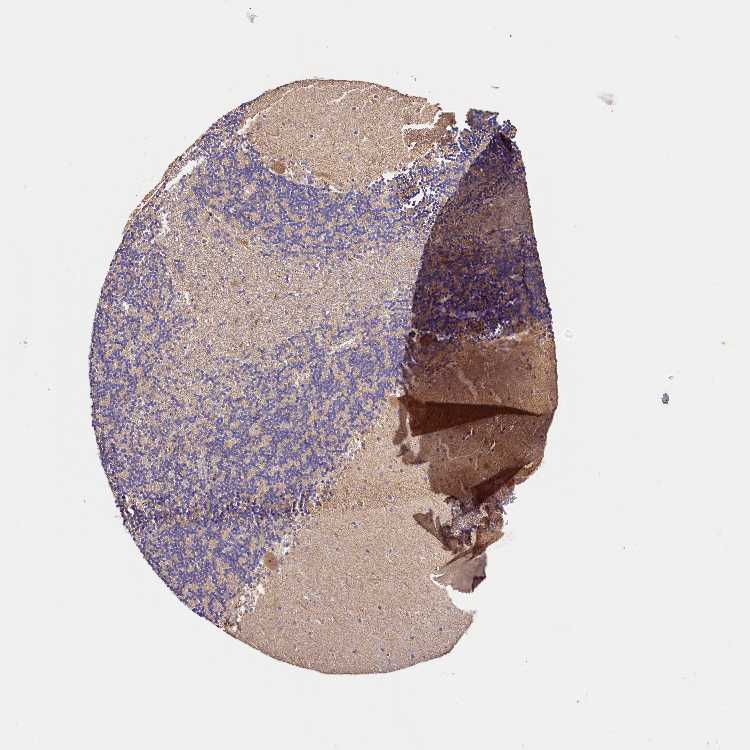

CEREBELLUM - Antibody stainingi

Antibody staining in the annotated cell types in the current human tissue is reported as not detected, low, medium, or high, based on conventional immunohistochemistry profiling in selected tissues. This score is based on the combination of the staining intensity and fraction of stained cells.

Each image is clickable and will lead to virtual microscopy that enables deeper exploration of all samples and also displays staining intensity scores, fraction scores and subcellular localization as well as patient and tissue information for each sample.

Antibody HPA041710Antibody HPA041796

Purkinje cells MediumLow

Cells in granular layer Not detectedLow

Cells in molecular layer Not detectedNot detected